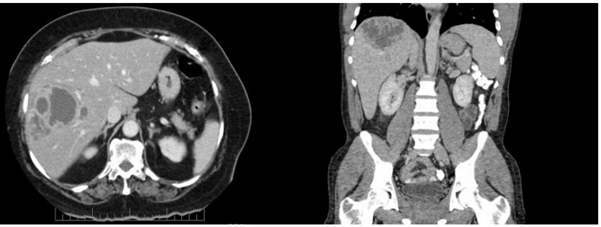

Paciente de 32 anos, sexo feminino, procurou o pronto-socorro por fraqueza, febre vespertina de até 39 ºC e dor em hipocôndrio direito há 4 semanas. Retornou da viagem de 1 semana ao Pará (proximidades de Santarém) 2 dias antes dos sintomas iniciarem. Exame físico: bom estado geral; anictérica; febril; hidratada; auscultas cardíaca e pulmonar normais; abdome doloroso à palpação em hipocôndrio direito; fígado palpável a 3 cm do rebordo costal direito; baço não palpável; algumas lesões de pele nas pernas. Exames laboratoriais: hemoglobina 11,9 g/dL; leucócitos 19.000/mm3; TGO 45UI/L; TGP 38UI/L; fosfatase alcalina 304 UI/L; gama-glutamiltransferase 268 UI/L; proteína C reativa 135. Tomografia computadorizada de abdômen apresentando a imagem a seguir:

Enunciado 1991512-1

Em relação ao caso, além de coletar hemoculturas, a conduta adequada é: